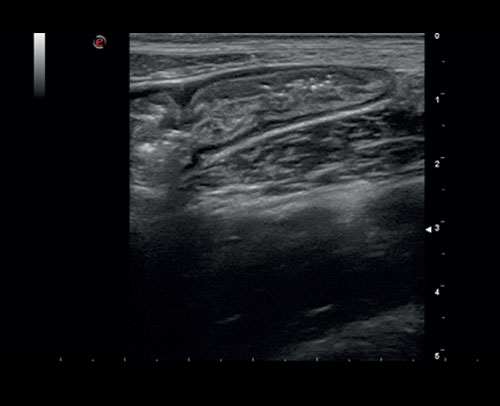

Léze štítné žlázy, zobrazení 2D s barevným dopplerem.